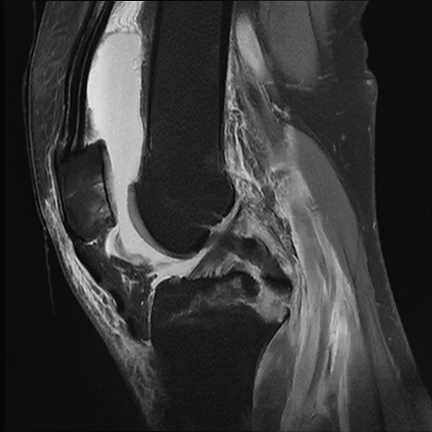

▲术前CT提示膝关节胫骨后交叉韧带止点撕脱骨折,

关节面不平